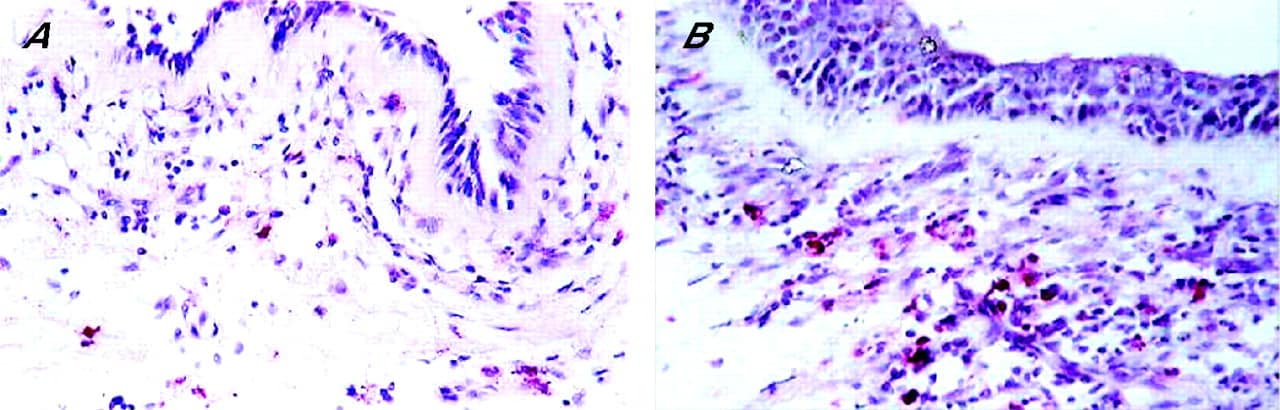

• الإصابة بالالتهابات بخاصة حين حدوث أي ألم بالجسم أو حدوث تورم أو احمرار مثل التهابات المفاصل الروماتويدية وكذلك بسبب التهاب حصى الكلى.